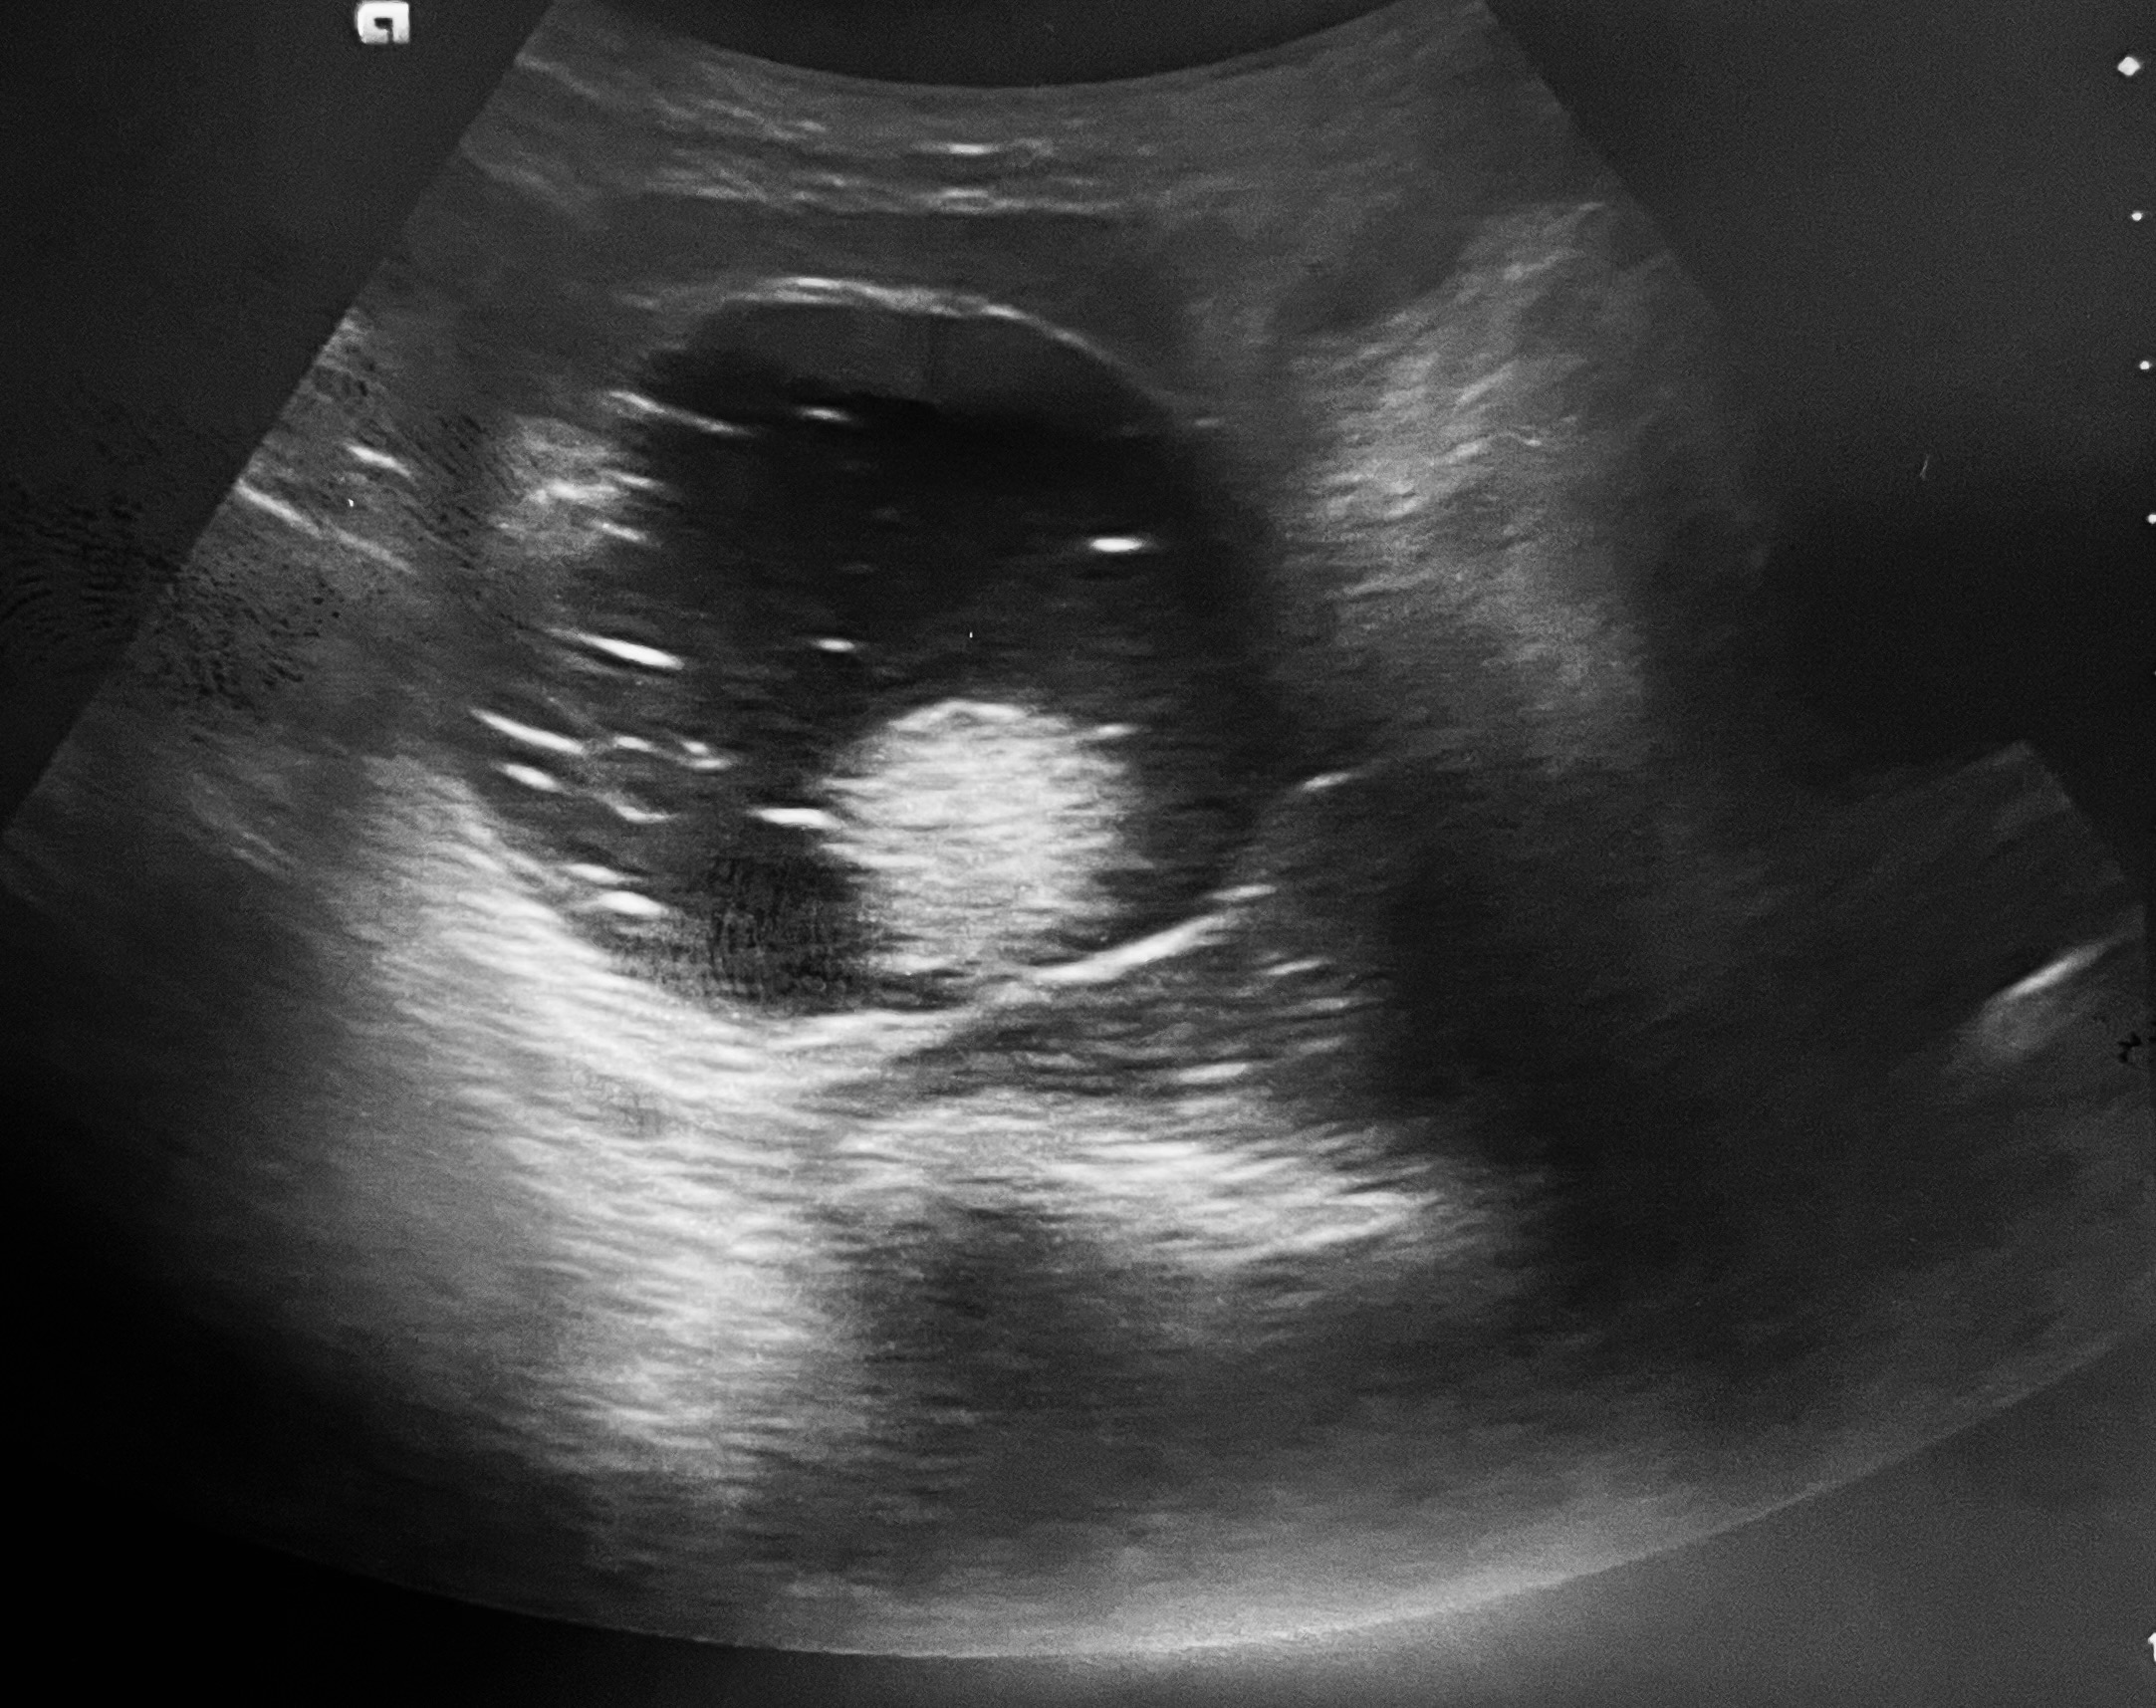

La ecografía clínica abdominal identificó una masa anexial heterogénea con áreas hiperecogénicas y refringentes, además de moderado líquido libre pélvico, hallazgos compatibles con lesión compleja de probable origen teratomatoso.

Ante estos datos se realizó interconsulta urgente a Ginecología, que mediante ecografía transvaginal confirmó múltiples imágenes anexiales heterogéneas con componentes sólidos y líquidos y focos hiperrefringentes sugestivos de teratoma dermoide.